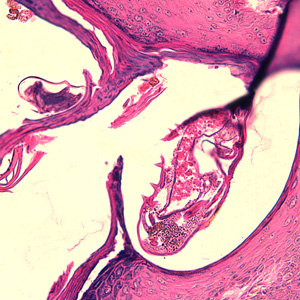

Case #244 – January, 2009

An 80-year-old resident of a long-term care facility presented with a skin condition manifesting as thick crusts over the skin accompanied by slight itching. The patient was originally treated for impetigo, with no resolution, and was ultimately admitted to the hospital for further testing. A skin biopsy was performed. The specimen was sectioned, stained with hematoxylin and eosin (H&E) and sent to a dermatopathologist for diagnostic assistance. Figures A–D show what was observed in the stained sections. Figures A and B were taken at 200x magnification. Figures C and D represent the same fields, respectively, taken at 400x magnification. What is your diagnosis? Based on what criteria?

Figure A